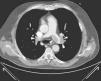

Caso clínico 3Uma mulher de 47 anos, obesa e com insuficiência venosa periférica, foi admitida no serviço de urgência por síncope, dispneia de início súbito, dor epigástrica, insuficiência respiratória grave e choque. Tinha iniciado toma de anticoncecional oral três dias antes da admissão. Poucos minutos após a admissão verificou‐se PCR em ritmo de atividade elétrica sem pulso (AESP), tendo sido iniciado SAV. Verificaram‐se vários episódios de recuperação de circulação espontânea seguida imediatamente de nova PCR. O ecocardiograma TT revelava dilatação das câmaras direitas (Figura 3A), IT grau III/IV (PSAP 45mmHg+PVC), fluxo pulmonar compatível com HTP e depressão da função sistólica do VD.

Por suspeita de choque obstrutivo por TEP de alto risco, realizou trombólise endovenosa com bólus de 50mg alteplase, com recuperação definitiva de circulação espontânea após cerca de 45 minutos de SAV. O angioTAC torácico mostrou focos tromboembólicos na porção distal de ambas as artérias pulmonares, na emergência das várias artérias lobares e de forma mais expressiva nos ramos segmentares da artéria lobar inferior direita (Figura 2). Por manter o quadro de choque refratário a medidas de suporte foi submetida a TR com AngioJet®, verificando‐se melhoria hemodinâmica imediata e melhoria angiográfica parcial. A doente permaneceu com suporte ventilatório e aminérgico durante dez dias, tendo tido evolução clínica favorável desde então com recuperação neurológica total. O ecocardiograma realizado um mês após o evento não evidenciava dilatação ou disfunção ventricular direita nem sinais sugestivos de HTP (Figura 3B). Teve alta ao final de 37 dias de internamento hospitalar.